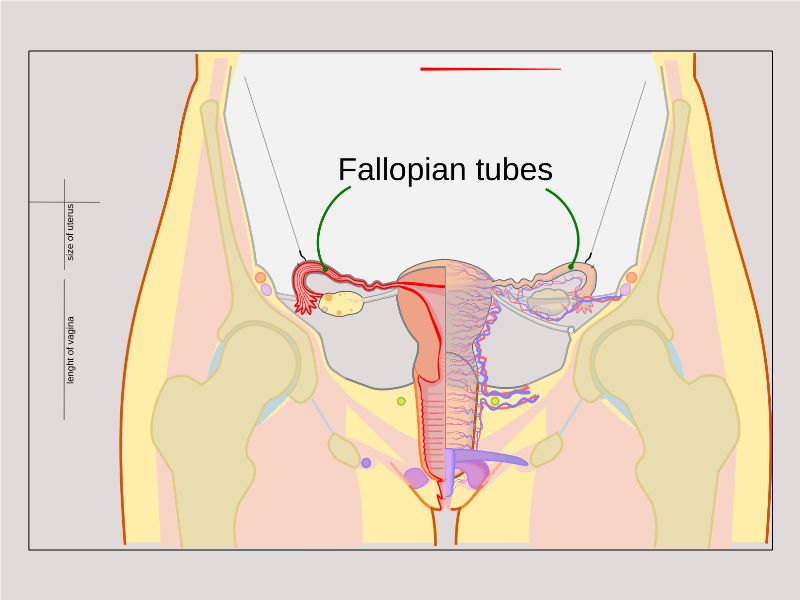

Tuba uterina

Also:

OviductFallopian tube

Uterine tube

Tuba uterina

- Muscular tube

- Most frequent site of fertilization

- Conveys zygote to uterus

- Four regions

- Three layers

Four regions

- Infundibulum

- Ampulla

- Usual site of fertilization

- Isthmus

- Pars interstitialis

- Passes through wall of uterus

Three layers

- Mucosa

- Muscular layer

- Serosa